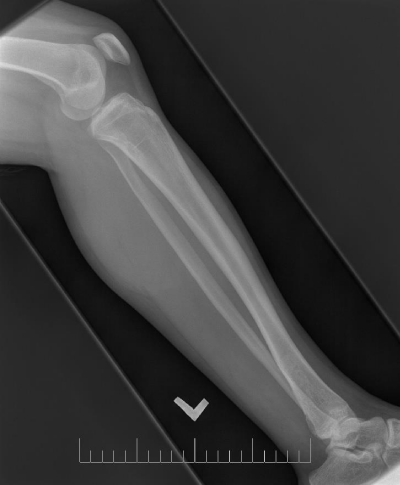

A 10-year-old female presented with left lower leg pain that had progressively increased over the duration of 1 year. On physical examination, tenderness was elicited on palpation of the distal tibia. Routine laboratory testing was normal. X-Ray was performed and revealed a lytic lesion with sclerotic margins in the left lower tibia (Figure 1). MRI was subsequently performed, demonstrating a left lower tibia lesion with low signal intensity on T1 weighted images (Figure 2), and high signal intensity on T2 weighted images (Figure 3). Pathology of the tumor revealed a diagnosis of a CMF. She was treated with curettage and autologous bone grafting (Figure 4). Post op eratively the left leg was immobilized with a plaster cast with restricted weight bearing (Figure 5). Follow up X-ray after 5 years demonstrates no tumor reoccurrence (Figure 6, Figure 7).

Figure 6: 5 year follow up AP X-ray of the left tibia/fibula.

Imaging is crucial to the diagnosis of this tumor. On X-ray the tumor appears as a space occupying radiolucent osteolytic lesion with sharp and well-defined margins (Figure 1). The margins are noted to be sclerotic (Figure 8) the tumor has no soft tissue component (Figure 9). There is no matrix calcification or visible periosteal reaction (Figure 10).

Figure 10: Initial AP X-ray of the left tibia/fibula.